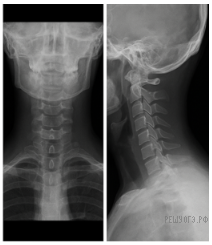

Версия для печати и копирования в MS WordКак называется прибор, изображенный на фотографии, с помощью которого получили данное изображение?

1) рентген-аппарат

2) спирометр

3) электрокардиограф

4) фонендоскоп

На фотографии изображен снимок, сделанный с помощью рентген-аппарата.

Ответ: 1.